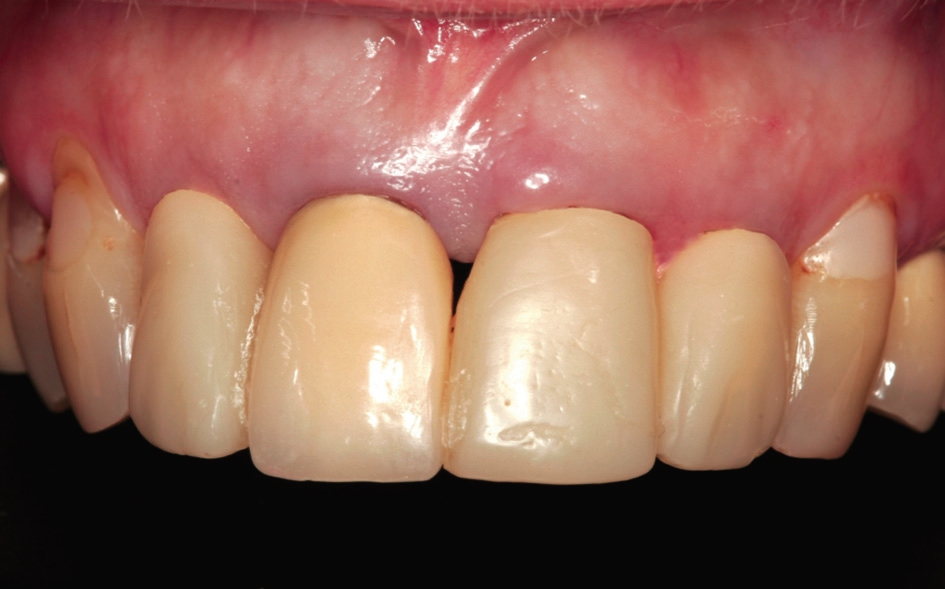

50 Jahre alte Patientin, Nicht-Raucherin ohne größere Risikofaktoren. Die radiologischen Aufnahmen zeigten insuffiziente Versorgung der maxillaren Frontzähne (11, 12, 21 und 22) mit Lockerungsgrad 3 und Knochenabbau bis in das obere Wurzeldrittel (Abb. 1).